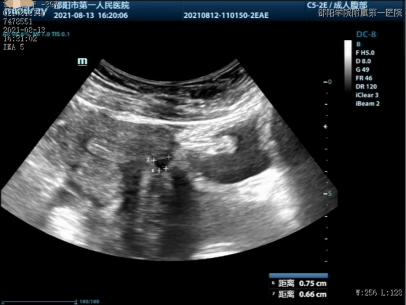

超声(2021-8-13):子宫前壁下段肌层内可见一大小约7.5mm*6.6mm的液暗区声像,考虑切口假腔;该处子宫肌层厚约3.2mm。